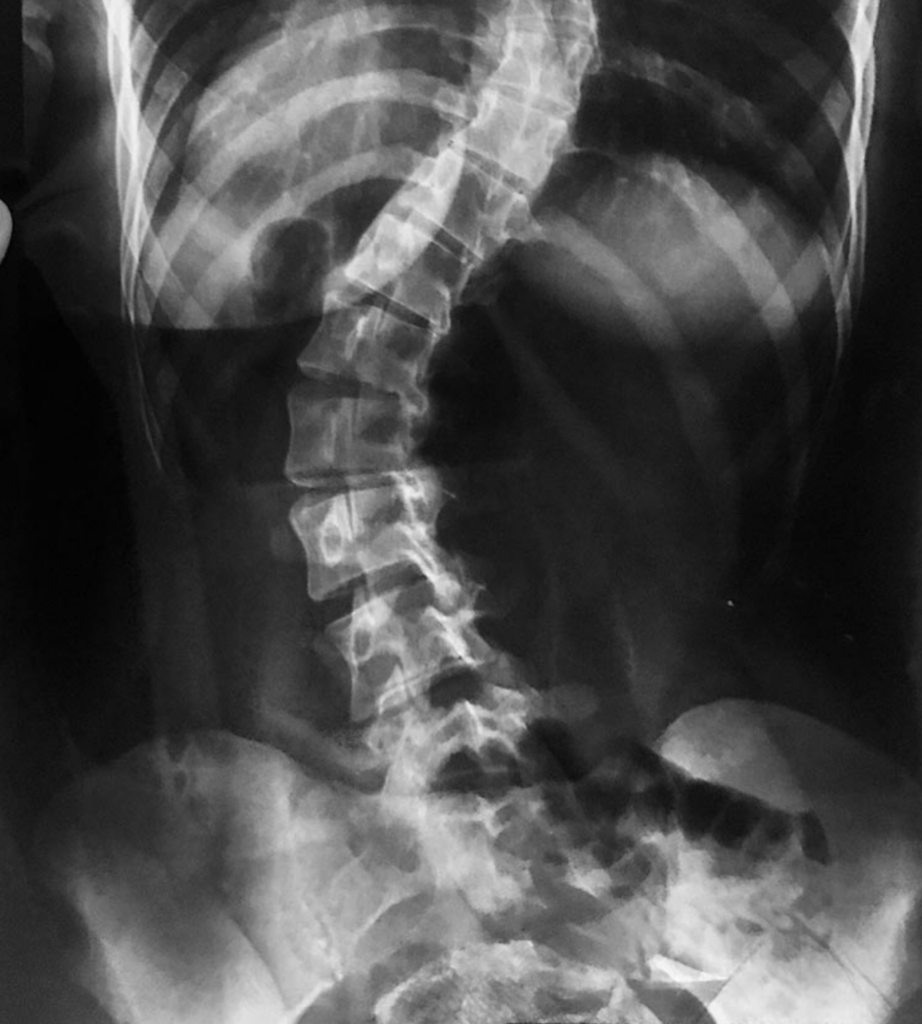

- Thực hiện chụp X-quang: Hình ảnh từ X-quang cho phép phát hiện những vị trí tổn thương nhỏ nhất ở các cột sống bị hẹp, hẹp lỗ liên hợp đốt sống, gai xương sống.

- Chụp cộng hưởng từ (MRI): Công nghệ chụp chiếu chẩn đoán bệnh tật tân tiến bậc nhất hiện nay. Hình ảnh có được sau khi chụp MRI không những chỉ ra rõ ràng dấu hiệu thoái hóa hẹp đĩa đệm, gai xương…mà còn phân tích chi tiết trạng thái và mức độ thoái hóa cột sống giúp bác sĩ đưa ra chẩn đoán chi tiết nhất.

- Chụp CT cắt lớp: Đây cũng là xét nghiệm thường được bác sĩ chỉ định cho người bệnh nghi ngờ mắc thoái hóa cột sống để tìm được nguyên nhân gây ra và xác định chính xác vị trí tổn thương.